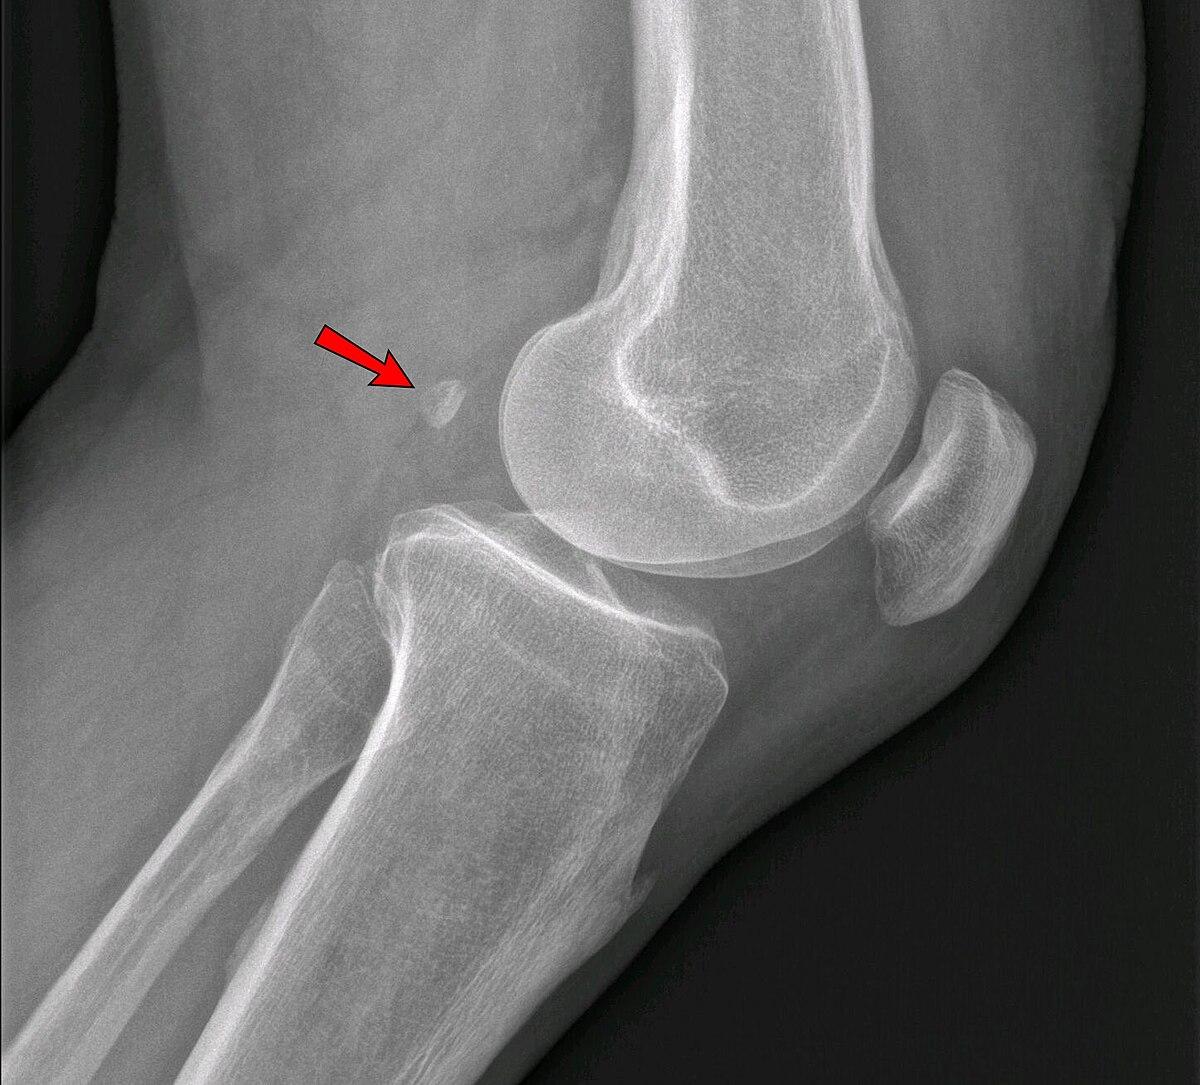

fabella는 라틴어입니다.

장딴지근 gastrocnemius muscle 외측두에 발생하는 종자뼈 sesamoid bone 를 말합니다.

많게는 1/3 정도가 가지고 있습니다

위키피디아에서 캡처했습니다.